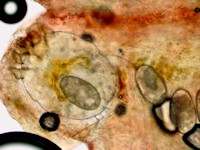

De huidschilfers zitten vol mijten en jongere mijtenstadia. Het volstaat om wat schilfers af te schrapen van een hyperkeratotisch schilferend gebied en daar een KOH-preparaat van te maken, daar moeten dan tientallen mijten en eieren in te zien zijn om de diagnose scabies crustosa te mogen stellen. Deze schilfers zijn zeer besmettelijk. Door het krabben kunnen de met schurftmijt beladen huidschilfers door de kamer dwarrelen en anderen besmetten (verzorgers, medepatiënten, bezoekers, huishoudelijk personeel). Als een patiënt met scabies Norvegica in een instelling verblijft is dat een risico voor het personeel en gelden strengere isolatiemaatregelen. Iedereen die in de kamer geweest is moet preventief worden behandeld met éénmalig ivermectine. Zie ook de richtlijn van het RIVM voor de aanpak van een uitbraak van scabies. In instellingen indien mogelijk de patiënt om de week verplaatsen naar een schone kamer en de oude kamer 1 week niet betreden.

Scabies mijten in het KOH preparaat

Mijten bij scabies crustosa Mijten bij scabies crustosa